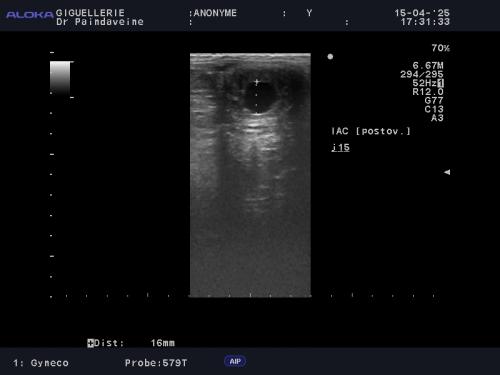

La précision du timing : Frais vs Congelé ?

Si l’insémination en semence fraîche ou réfrigérée offre une certaine souplesse, le recours à la semence congelée (IAC) exige une précision chirurgicale. La survie des spermatozoïdes cryoconservés étant réduite, le suivi devient intensif pour garantir un dépôt de semence au plus proche de l'ovulation.